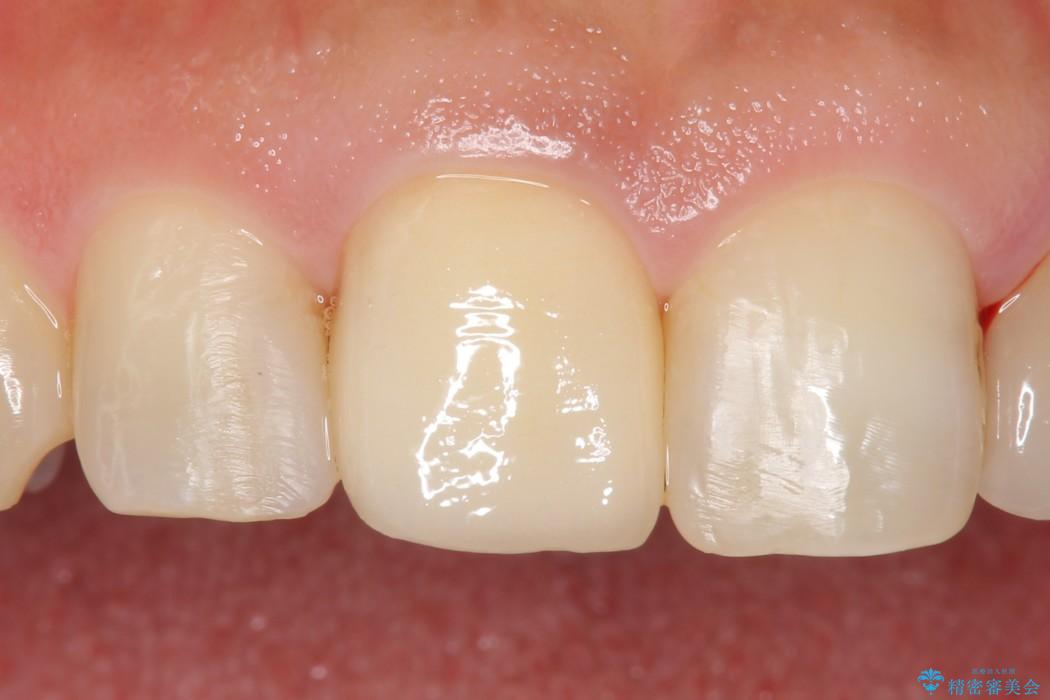

治療後について

今回のケースでは丁寧に虫歯を取りきることにより、神経を保存することができました。